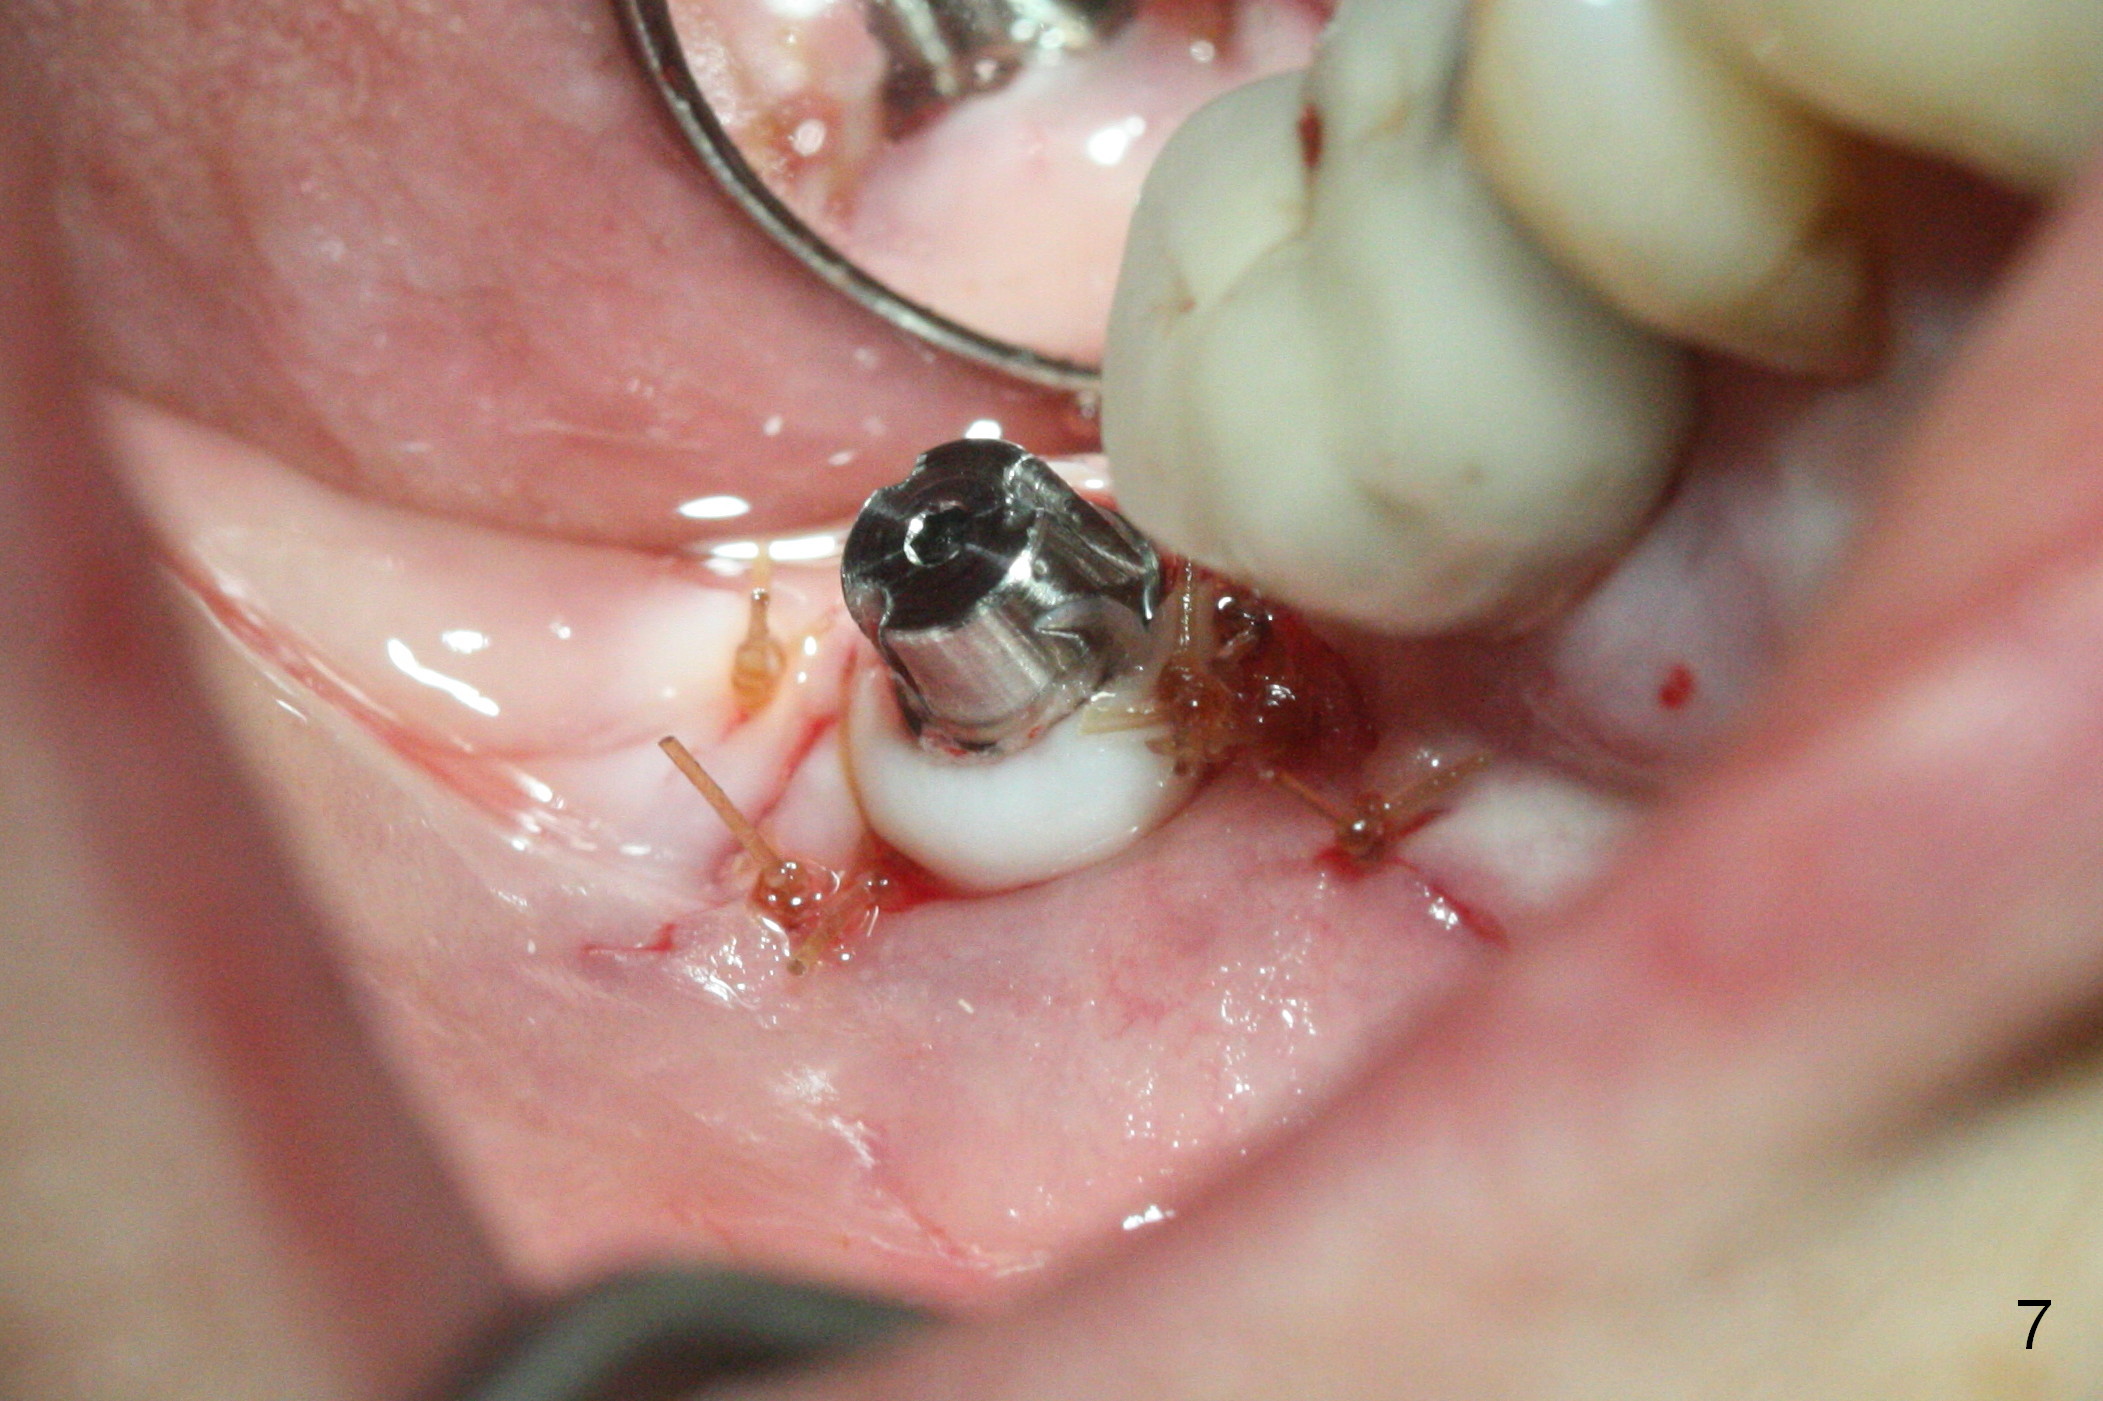

Initial osteotomy at the site of #31 using 2 mm pilot drill for 11 mm appears to be distal by 2-3 mm (Fig.1, Fig.10 A (circle, occlusal view of the edentulous and dentate (#29 and 30) areas)). Lindamann bur is used to move the osteotomy (Fig.8 white rectangle, Fig.10 B). It seems that the osteotomy returns distal as the osteotomy increases (Fig.2 (5x17 mm tap), Fig.8 arrow, Fig.10 C (green circle)). It appears to be late to change; a 5x17 mm tissue-level implant is placed with > 60 Ncm (Fig.3-5). The buccal and lingual rough surface of the implant (Fig.5 *) is covered by autogenous bone/Osteogen and Collagen Dressing (Fig.6 *). After suturing (Fig.7), periodontal dressing is applied around the abutment (Fig.5 A (4.5x3 mm)).